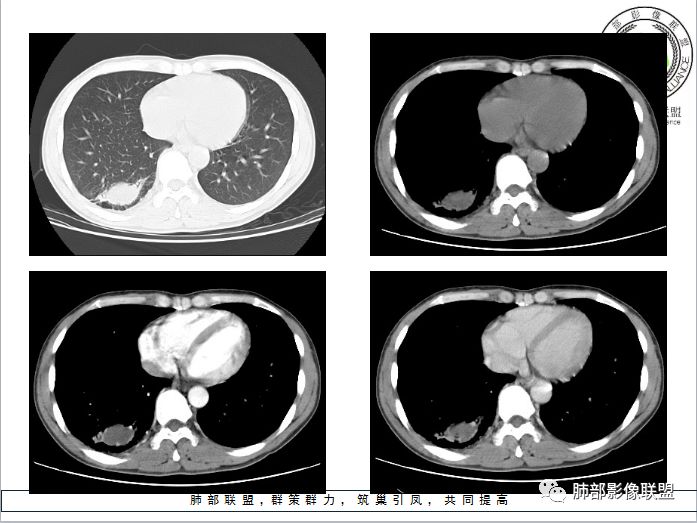

小赵:青年男性,慢性咳嗽,低热,血沉略快。右肺类圆形肿块,密度偏低,周围见条索,较低层面似见卫星灶,邻近胸膜增厚。增强扫描薄膜样强化。综合考虑结核可能

市医院-时建文:青年男性,慢性咳嗽,低热,右肺类圆形肿块,密度偏低,周围见条索,血管贴边,邻近胸膜增厚。结核?psp?

一米阳光:右肺下叶后基底段长圆形病变,边缘清晰,中心部密度减低,增强病变前缘见血管影,略环形强化,病变周围见点状及索条影,结合年轻病史,考虑结核

甄德强:右肺下叶结节影,边缘见多条软毛刺,包膜样强化,卫星病灶,考虑结核,不除外合并曲霉

大雄:似乎是支气管相连续,无强化,平扫似有高密度,考虑支扩粘液栓(曲霉所致)

小微:青年男性,慢性咳嗽,低热,血沉快。右肺类圆形肿块,其内见低密度影,周围见条索,较低层面似见卫星灶,邻近胸膜增厚。增强扫描薄膜样强化,其内为低密度坏死。综合考虑结核可能。有血管贴边,待除外PSP

弹指之间:1. 青年男性,慢性咳嗽,低热,血沉快。2. 右肺下叶类圆形肿块,周围见条索,较低层面似见卫星灶,邻近胸膜增厚。增强后见轻度延迟强化,见血管贴边征,肺门侧见小淋巴结影(肺静脉起始处肿大淋巴结不确切);3. 右肺下叶体积未见缩小,局部支气管不扩张,无钙化;综合考虑结核可能,PSP和小细胞肺癌待排

男,34岁,主诉:间断性咳嗽伴右胸反复不适半年;现病史:右胸不适,深呼吸加重,伴轻度咳嗽、低热;

青年男性、病史半年,低热;

右肺下叶囊性病变,边缘光滑,薄环状强化,内壁较光滑

血管贴边

周围多发长索条

远端有斑片状条带状高密度影,周围肺气肿

附近胸膜增厚,内有血管影